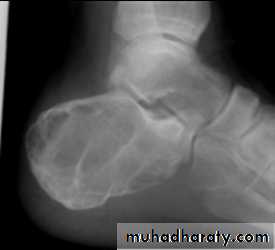

is pathognomonic. There is a

well-defined exostosis emerging from the metaphysis,its base co-extensive with the parent bone.

It looks smaller than it feels because the cartilage cap is usually invisible on x-ray.

The x-ray appearance

Large lesions may have a ‘cauliflower’

appearance, with degeneration and calcification in the Centre of the cartilage cap.30